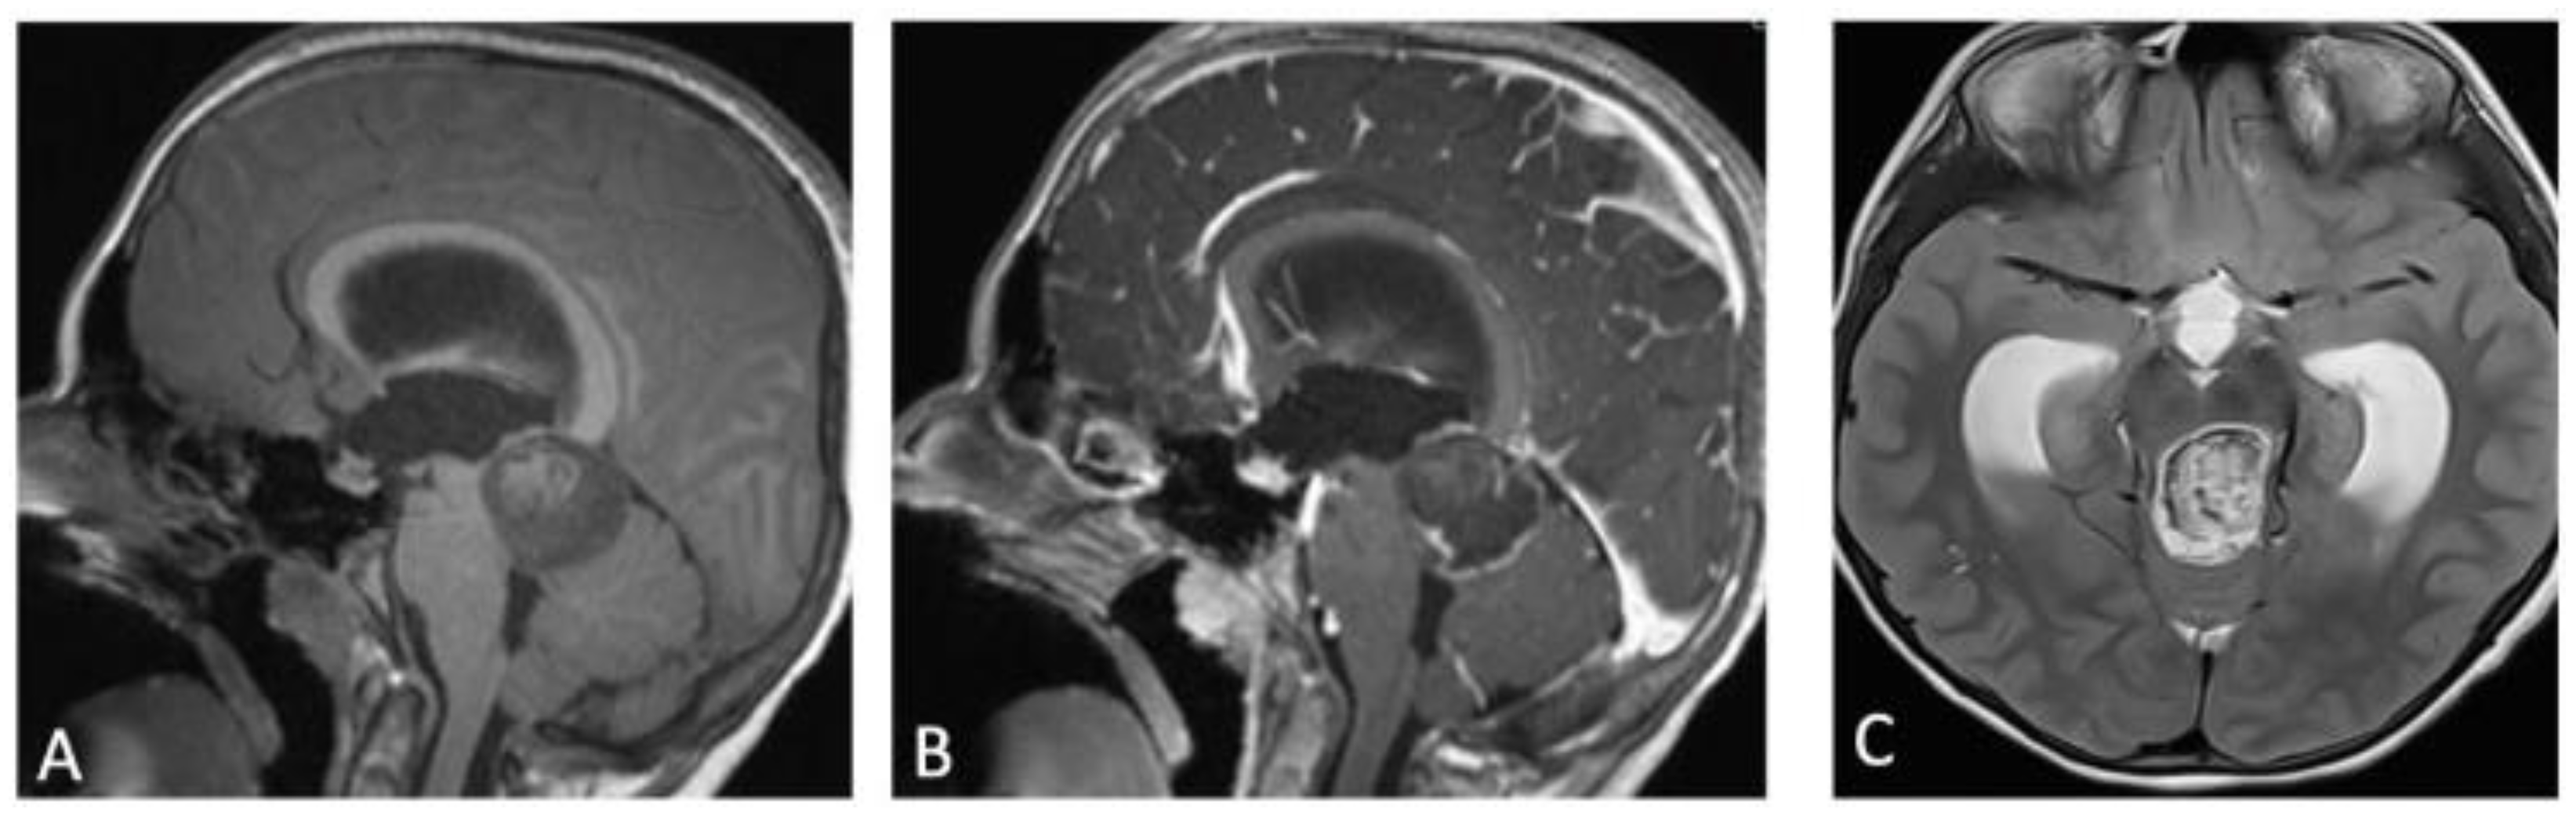

2. Case Presentation